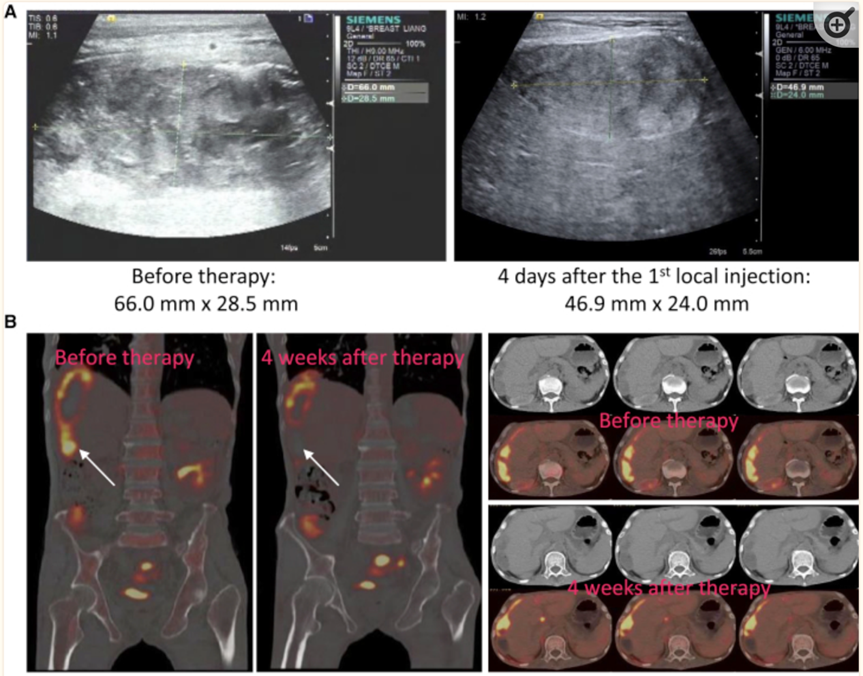

该研究中接受NK细胞治疗的是3 例转移性结直肠癌患者。当前两名患者接受了低剂量的CAR-NK细胞腹腔内输注后,实验数据观察到腹水生成量明显减慢以及腹水样本中肿瘤细胞的数量急剧减少。第三例肝转移癌症患者采用超声引导下瘤内经皮注射和腹腔内灌注方式输注 CAR-NK细胞后,经多普勒超声检查,观察到肝部肿瘤也快速缩小。